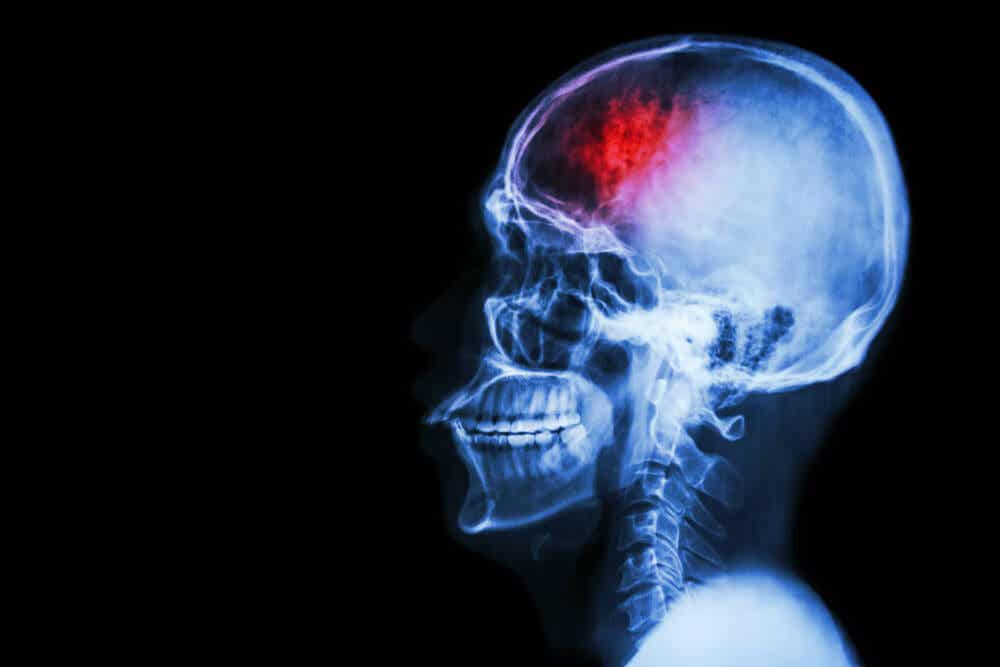

Problem ten rozwija się, gdy krew gromadzi się wewnątrz kości czaszki. Miejsca zbierania się krwi są zróżnicowane, a obraz kliniczny będzie się zmieniał w zależności od tych pozycji.

Jednym z problemów tych krwiaków jest nacisk, jaki generują na wrażliwy narząd, jakim jest mózg. To zwiększone napięcie uszkadza neurony i zakłóca ich funkcjonowanie.

Nagromadzenie krwi pochodzi z pękniętego naczynia krwionośnego w czaszce. Może być ono przerwane przez uraz lub przez samoistne pęknięcie tętnicy, na przykład w przypadku wad wrodzonych.